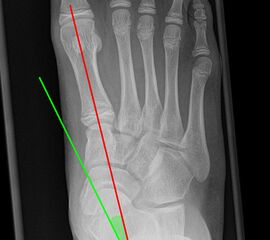

Vermessung der belasteten Aufnahmen des Fußes

Winkelmessungen am Fußskelett beziehen sich sämtlich auf belastete Aufnahmen 6. Die folgenden Aufnahmen zeigen die üblicherweise verwendeten Winkelmaße und ihre Definition. Viele Fehlstellungen des Fußes betreffen den Vor- und Rückfuß. Dies sollte bei der Beurteilung der Bilder und der Therapieplanung stets berücksichtigt werden.

Beurteilung von Fehlstellungen des Vorfußes

Zur Vollansicht und zum Lesen der Bildbeschreibung bitte die Bilder anklicken.

Gelenkflächenwinkel

DMAA (Distal metatarsal artikular angle, Syn. Gelenkflächenwinkel): Winkel zwischen der Achse des Os metatarsale I (rot) und dem Lot auf die distale Gelenkflächenebene (blau) des Os metatarsale I. Die Gelenkflächenebene (grün) wird definiert durch zwei Punkte, welche die mediale und laterale Begrenzung der Gelenkfläche definieren (Norm: <10° 5). Die Projektion des DMAA ist stark abhängig von der Rotation des Os metatarsale I 7. Daher ist bei der operativen Behandlung des Hallux valgus eine Beurteilung häufig erst nach Korrektur der Pronationsstellung des Os metatarsale I möglich. Tendenziell wird der DMAA auf präoperativen Röntgenaufnahmen überschätzt.

Beurteilung eines Metatarsus adductus

Medial wird eine Linie von der medialen Begrenzung des TMT1-Gelenks und der medialen Begrenzung des Talonavikulargelenks (TN) gezeichnet. Auf der lateralen Seite des Fußes wird eine zweite Linie von der lateralen Begrenzung des Calcaneocuboid-Gelenks (CC) zur lateralen Begrenzung des TMT5-Gelenks gezeichnet. Die Mittelpunkte beiden Linien werden verbunden (blau). Der Winkel zwischen der Achse des Os metatarsale II (rot) und dem Lot auf Verbindungslinie (grün) ist ein Maß für die Stellung des Vorfußes zur Fußwurzel. Dieser Wert dient zur Charakterisierung eines Pes adductus. Ein Pes adductus kann zu einem normwertigem Intermetatarsale I/II Winkel führen, obwohl klinisch eine ausgeprägte Hallux valgus Deformität vorliegt 8. (Norm: ±13° 9.